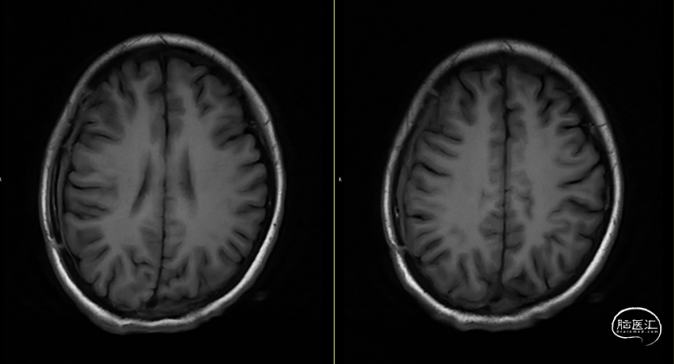

第3次术后16天,复查颅脑MRI(如上图),硬膜外及皮下异常信号较前明显减少,负压引流管引流不明显,拔除负压引流管,继续使用头孢曲松+多西环素口服联合抗炎治疗。